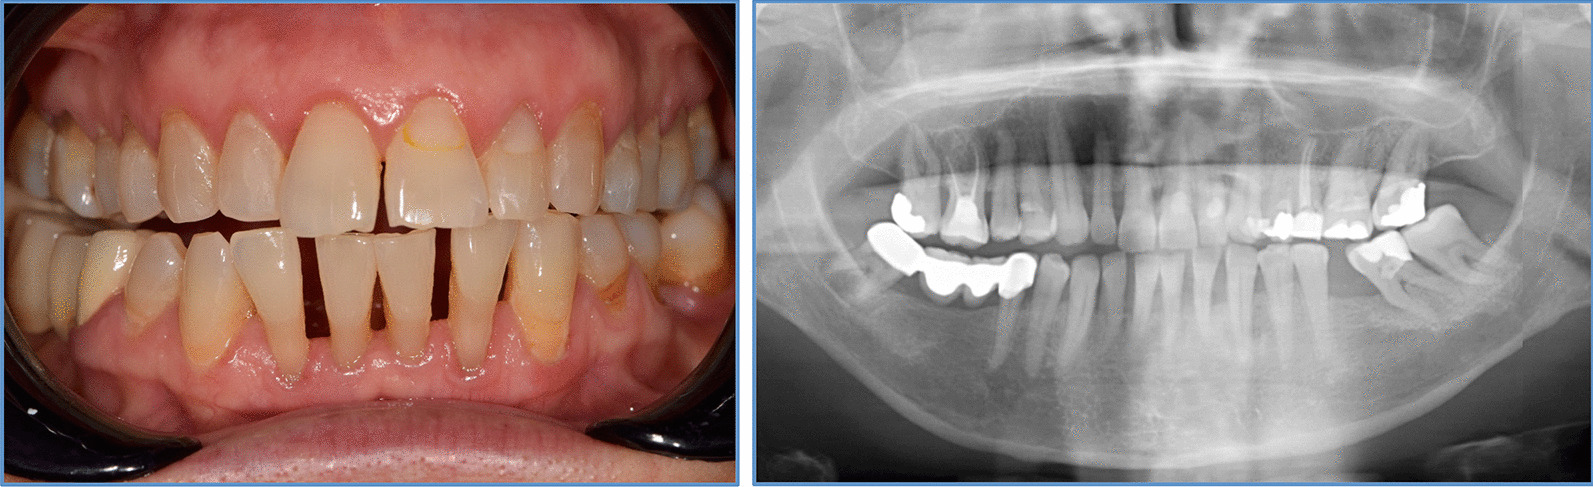

Periodontal diagnosis was made according to the 2017 classification for periodontal and gingival diseases [20] under consideration of clinical presentation and patients’ medical history. Participants were categorized based on their periodontal status into periodontitis (Stage I/II-Moderate and Stage III/IV-Severe) or non-periodontitis (gingivitis and healthy). Individuals were diagnosed with periodontitis if interdental CAL was detectable at ≥ 2 non-adjacent teeth, or if buccal/oral CAL ≥ 3 mm with pocketing > 3 mm at ≥ 2 adjacent teeth was present. Periodontitis patients were grouped as ‘’severe periodontitis’’ (Stage III and IV), if they had a history of tooth loss due to periodontitis, CAL ≥ 5 mm and/or PD ≥ 6 mm and/or vertical bone loss ≥ 3 mm and/or furcation involvement grade 2 or 3 was present. Milder cases were recorded as ‘’moderate periodontitis’’ (Stage I and II). PD ≤ 3 mm and BOP ≥ 10% was recorded as ‘’gingivitis’’. Individuals with PD ≤ 3 mm and full mouth BOP < 10% were recorded as ‘’healthy’’. Figure 1 shows clinical and radiographic images from one representative within the postmenopausal group with clinically diagnosed periodontitis.

Fig. 1.

Clinical and radiographic images of a representative patient from the postmenopausal group with periodontitis diagnosis